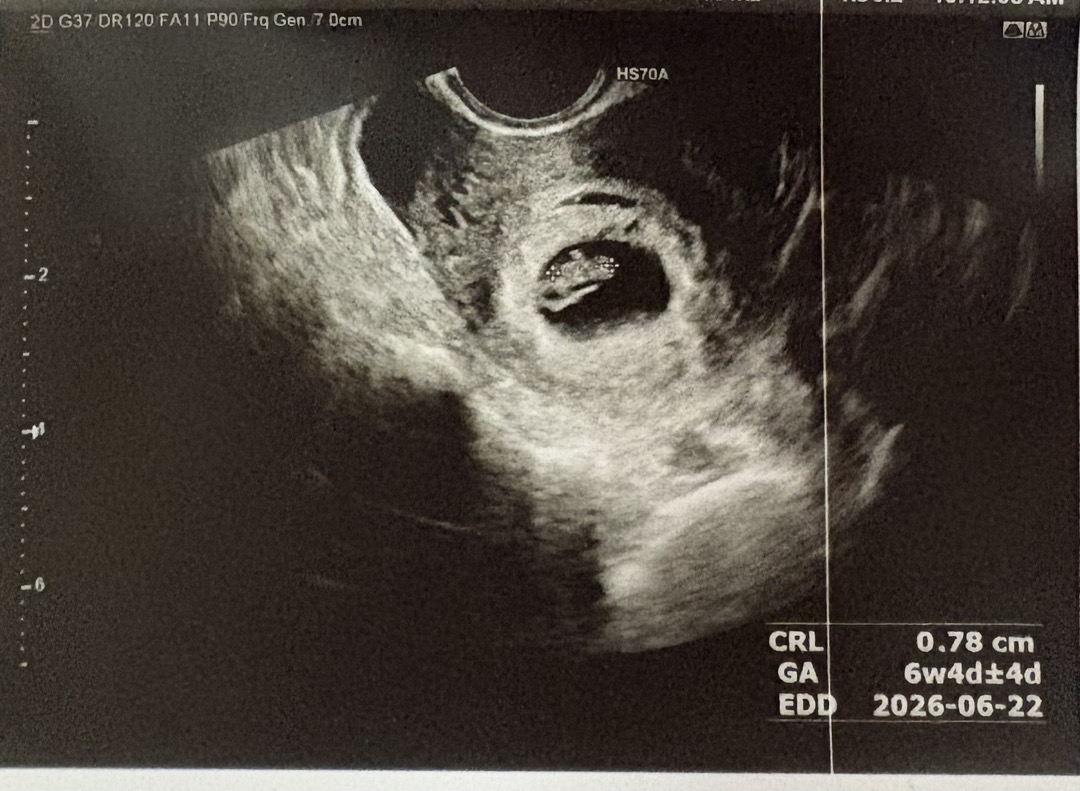

안녕하세요. 6주 4일차 젤리곰 자랑할게요 ㅎㅎ

저는 애기집만 있을 줄 알았는데 심장소리도 들려서 진짜 놀랬어요 ㅎㅎ 진짜 눈물나더라고요ㅠㅠ

저는 오늘 듣고왔는데 진짜 심장소리 듣자마자 눈물이ㅠㅠ 임신초기라 너무 걱정했는데 일정하게 잘뛰고있는거 보고 너무 감사했어요